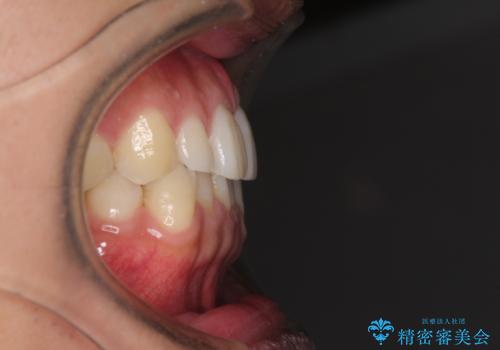

前歯のデコボコとクロスバイト インビザライン矯正治療

- 前歯のデコボコとクロスバイトを治したいとのことで来院された患者様です。

上下顎ともに歯列全体の側方拡大を行い、下顎前歯はIPR(歯と歯の間を削る)によってデコボコとクロスバイトが解消するように設計し、インビザラインにより治療を行うこととしました。

2年弱で終了する予定でしたが、途中来院されなかった時期があり、その後舌側転位している前歯を動かせるところまで動かしたいとのことで4年ほど治療を継続されました。